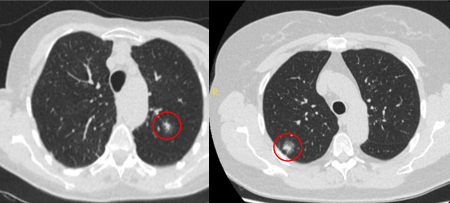

Computed tomography (CT) showing two areas (red circles) of mucoid impaction of the left upper lobe subsegmental bronchi, resulting in appearance that mimics a nodule

From the collection of Dr George Tsaknis, MD, PhD, FRCP(London), MRQA, MAcadMEd, PGCert; used with permission